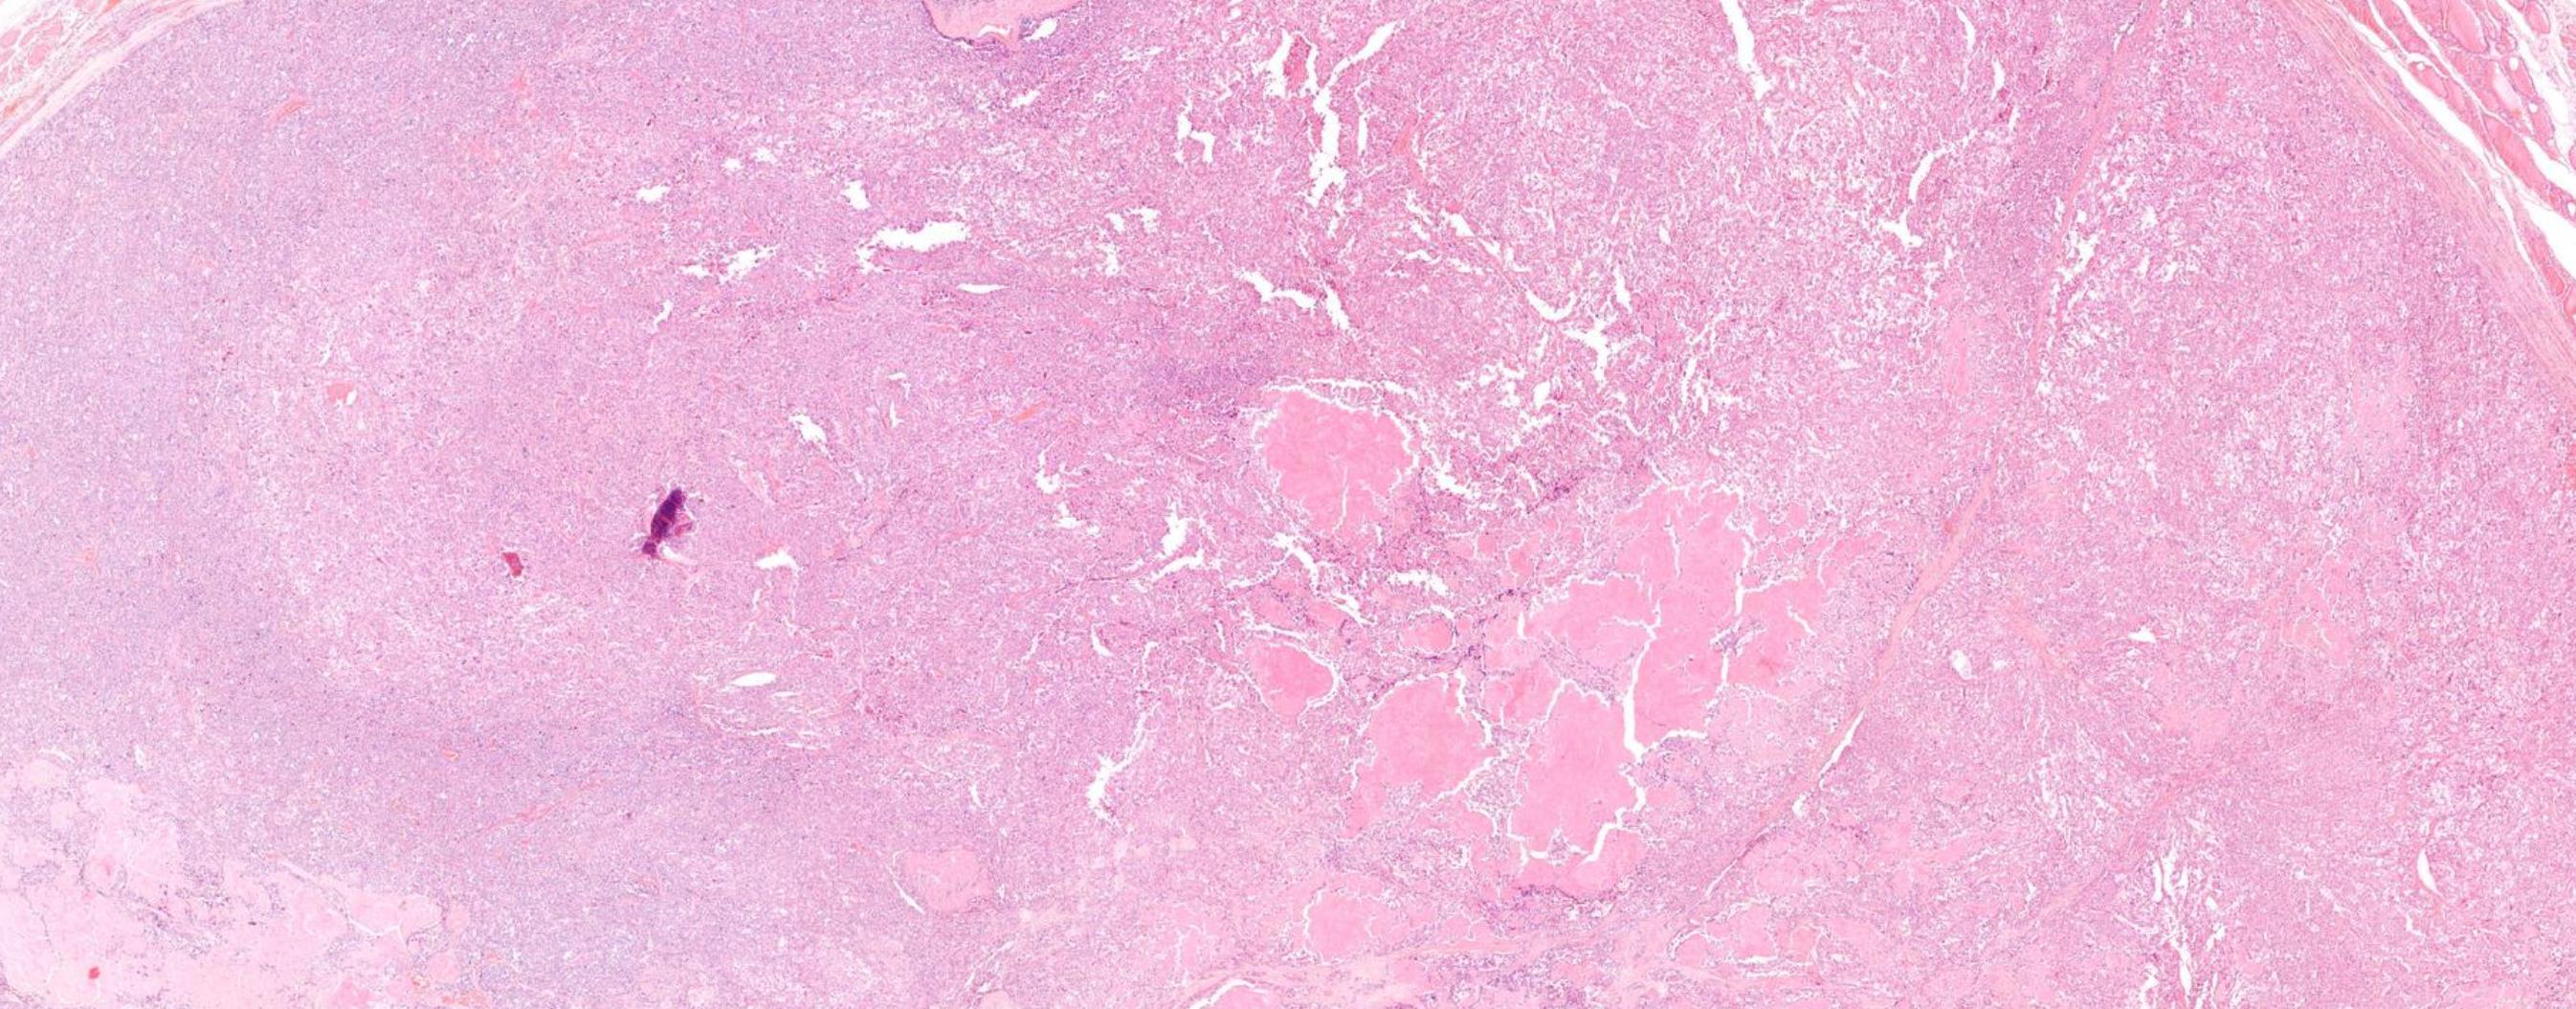

Case 8

Female 51 years Thy 3a left hemithyroid.

Case 8 Diagnosis

Poorly differentiated thyroid carcinoma arising possibly in a columnar cell variant of Papillary thyroid carcinoma

Discussion-Follicular-derived carcinomas, high-grade Subtypes • Poorly differentiated thyroid carcinoma (PDTC)- Insular carcinoma • Differentiated high-grade thyroid carcinoma (DHGTC) Turin consensus criteria for PDTC (i) presence of a solid/trabecular/insular pattern of growth in a tumour diagnosed as malignant based on invasive properties; (ii) absence of conventional nuclear features of papillary carcinoma; (iii) presence of at least one of the following: convoluted nuclei, mitotic count ≥ 3 per 2 mm2 , tumour necrosis DHGTC- ≥ 5 mitosis per 2 mm2 in hot spot + tumour necrosis, at least partially preserved normal tumour histology and immunoprofile

Immunoprofile • Positive for keratins, thyroglobulin, TTF1, and PAX8 • Thyroglobulin expression is typically reduced

• Ki67/MIB-1 usually 10-30%

and focal in poorly differentiated areas often with a peculiar dot-like paranuclear pattern.